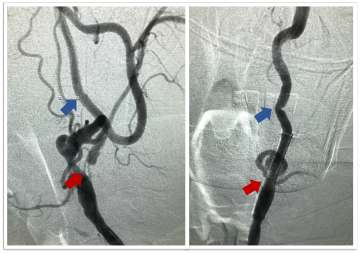

- Carotid Artery Stenting: This is a newer endovascular procedure performed from the inside of the blood vessels to open the stenosis. The surgeon uses small tubes and wires inserted into the wrist or groin arteries, navigated to the carotid artery in the neck. An umbrella is positioned above the narrowing to catch any debris and a stent is delivered to dilate the region of stenosis and hold the vessel open, improve flow and prevent future strokes (Figures 3 and 4).